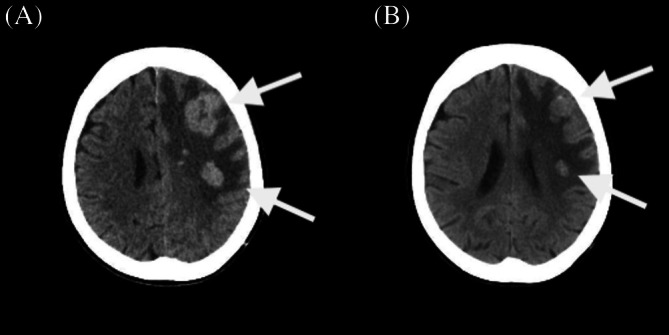

Lorlatinib Achieved Rapid CNS Response in an 81-Year-Old NSCLC Patient With Performance Status Deterioration.

Lorlatinib may offer rapid CNS symptom and imaging improvement after alectinib failure, even in elderly ALK-positive NSCLC patients with declining performance status.